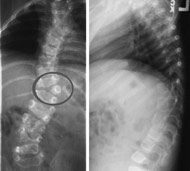

Полупозвонки (клиновидные позвонки) - врожденная патология, при которой развивается только половина позвонка, что ведет к искривлению позвоночника.

Эта патология не поддается консервативному лечению. Полупозвонки требуют хирургического удаления в возрасте 3-5 лет; это позволяет избежать формирования сколиоза. Если полупозвонки не удалены, то операция возможна в подростковом возрасте с использованием методики Котреля - Дюбуссе - Ленке.